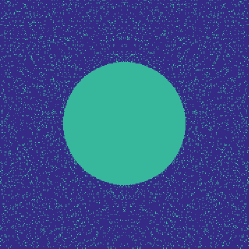

Figure 1 illustrates the best performing randomized indices and our learned set of indices in the plane of the -space. Both the variable density approach [14] and our learning-based approach concentrates its sampling budget on the low frequencies, however the latter is endowed with the capability to adapt its frequency selection to the frequency content of the training signals instead of assuming a circularly symmetric selection.